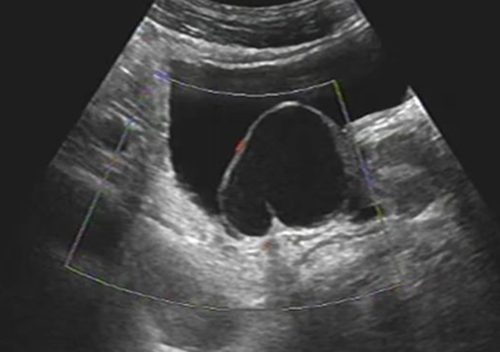

精囊囊肿声像图:囊性肿块嵌入在膀胱腔内,运用嵌入器官征思维方法,提示该囊性肿块来源于膀胱之外